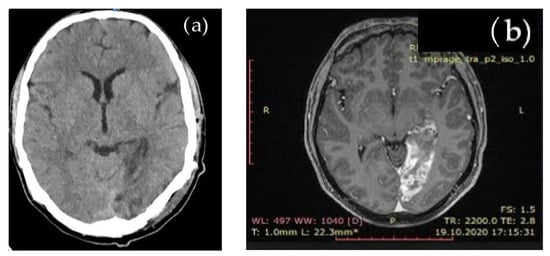

Due to stroke, suggesting symptoms, cerebral native CT and subsequent brain MRI evaluation showed an acute left occipital ischemic lesion, shown in Figure 1.

Figure 1.

Cerebral imaging: (a) native brain CT aspect: left occipital ischemic hypodense lesion; (b) brain MRI aspect: left occipital ischemia.

The brain MRI detected an acute ischemia in the left occipital area, excluding other types of cerebral lesions.